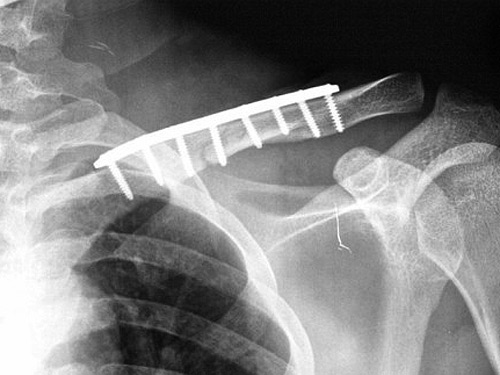

Sebastián Castella fue operado con éxito e la noche del sábado pasado, tras haber sufrido la fractura de la clavícula izquierda cuando fue alcanzado por un toro de la ganadería de Las Ventas del Espíritu Santo en la penúltima corrida de la Feria de la Macarena de la ciudad colombiana de Medellín.

La operación fue realizada en el Hospital Pablo Tobón Uribe y tuvo una duración de dos horas y media en la que, según el parte médico posterior, se consiguió reparar la fractura, con desplazamiento de la clavículo, y se realizó la inmovilización correspondiente para continuar con el proceso de recuperación.

La operación fue realizada en el Hospital Pablo Tobón Uribe y tuvo una duración de dos horas y media en la que, según el parte médico posterior, se consiguió reparar la fractura, con desplazamiento de la clavículo, y se realizó la inmovilización correspondiente para continuar con el proceso de recuperación.